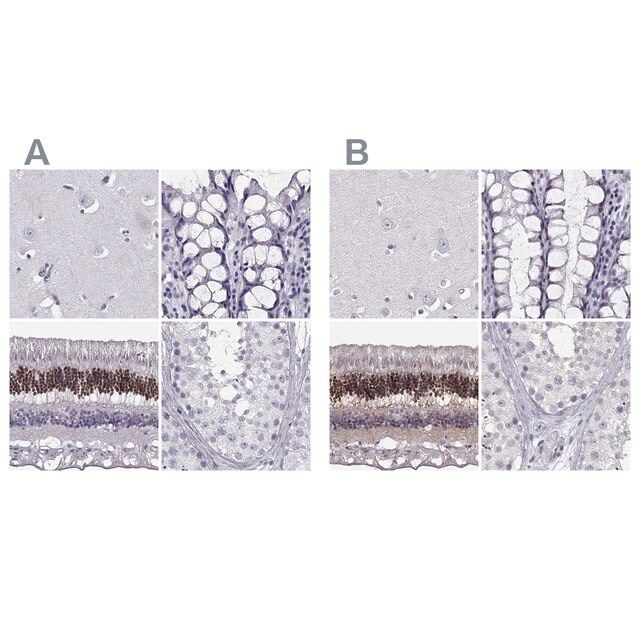

人类蛋白质图谱项目可细分为三个方面的工作:人类组织图谱、癌症图谱和人类细胞图谱。支持 Tissue and Cancer Atlas 项目而产生的抗体,已经通过免疫组化针对数百个正常和疾病组织进行了测试,通过 Human Cell Atlas 项目最近的努力,很多已经通过免疫荧光法进行了表征,不仅在组织级别,现在也在亚细胞级别绘制了人类蛋白质组图谱。通过点击图像库链接,可以在 Human Protein Atlas (HPA) 位点上查看这些图像和这个庞大数据集的集合。要查看这些协议 和其他有关 Prestige 抗体和 HPA 的有用信息,请访问sigma.com/prestige。

Prestige Antibodies®是经过高度表征和广泛验证的抗体,同时还有一个优点是其每个靶标的所有可用表征数据都可以通过位于此页面顶部产品名称下方的人类蛋白质图谱门户进行访问。Prestige Antibodies®对其他蛋白质的独特性和低交叉反应性是通过严密的抗原区域选择、亲和纯化和严格的选择来实现的。针对每一个Prestige Antibody都存在有对应的Prestige抗原对照,并可在链接区域内找到。

- 44例正常人类组织以及20例最常见癌症类型组织的IHC组织阵列。